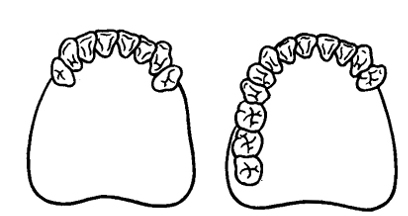

Kerámia alapú cirkónium-oxid elengedhetetlen fellendülés az elülső fogak - az általa a legtermészetesebb formája, ami különösen fontos az elülső fogak. A használata teljesen kerámiából protézis, amikor teljesen kiküszöböli annak kockázatát, allergiás reakciók, amelyek előfordulhatnak a fém jelenléte a szájban.

Kerámia alapú cirkónium-oxid keletkezik a fehér keret. Íny, míg világít belülről, amely megteremti a hatása egy természetes fog.

- ejtik overbite;

- jelenlétében alacsony klinikai természetes fog magassága (kis fogak);